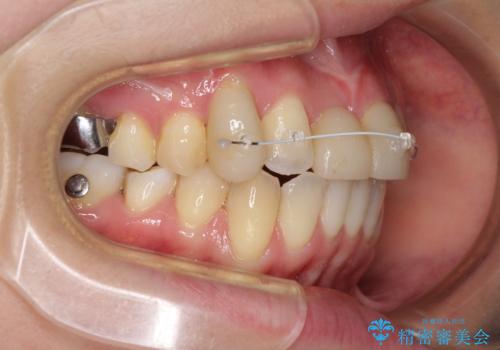

- 矯正装置

- インビザライン

本来であれば積極的に小臼歯を抜歯して口元を下げても良いのですが、前歯を1本抜歯しないといけなくなったため、非抜歯矯正をインビザラインを用いて行うこととしました。

補助装置により上顎歯列を遠心移動させたため、非抜歯でしたが口元の突出感をある程度改善させることができました。

欠けてしまった前歯もオールセラミッククラウンにて自然に補綴することができました。